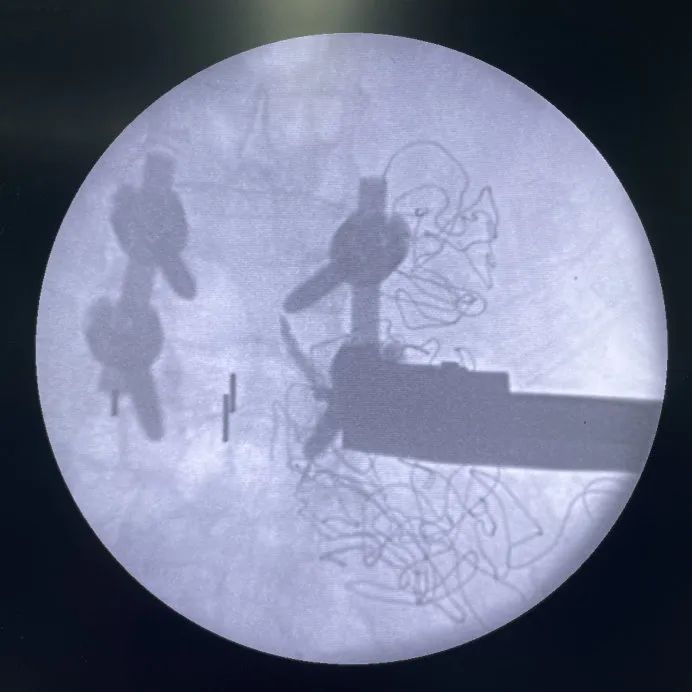

示意-正視圖:頭側(cè)固定夾打入已完成,尾側(cè)正在使用固定夾開路器開路

示意-側(cè)視圖:頭側(cè)固定夾打入已完成,尾側(cè)正在使用固定夾開路器開路

L3/L4常規(guī)OLIF融合器植入

L3/L4 、L4/L5椎間植骨